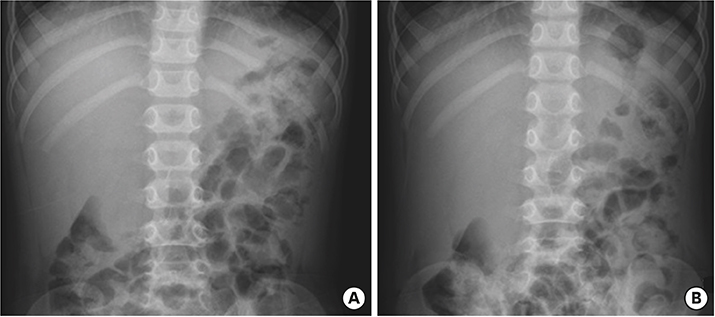

Laboratory findings showed neutrophilic leukocytosis (22,560 cells/mm3, with 81% neutrophils), elevated erythrocyte sedimentation rate (118 mm/hr), C-reactive protein (CRP) (19.8 mg/dL), brain natriuretic peptide (BNP) (1,022 pg/mL), and decreased sodium (131 mEq/L). Liver function tests were hyperbilirubinemia (total bilirubin, 3.4 mg/dL) as well as elevation of aspartate transaminase (AST) (155 U/L) and alanine transaminase (ALT) (418 U/L). His abdomen radiograph revealed modest shadowing of GB distension and no specific findings (Fig. 1A and B).

Fig. 1

Abdominal radiograph supine view (A) and erect view (B) indicated modest shadowing of gallbladder distension.